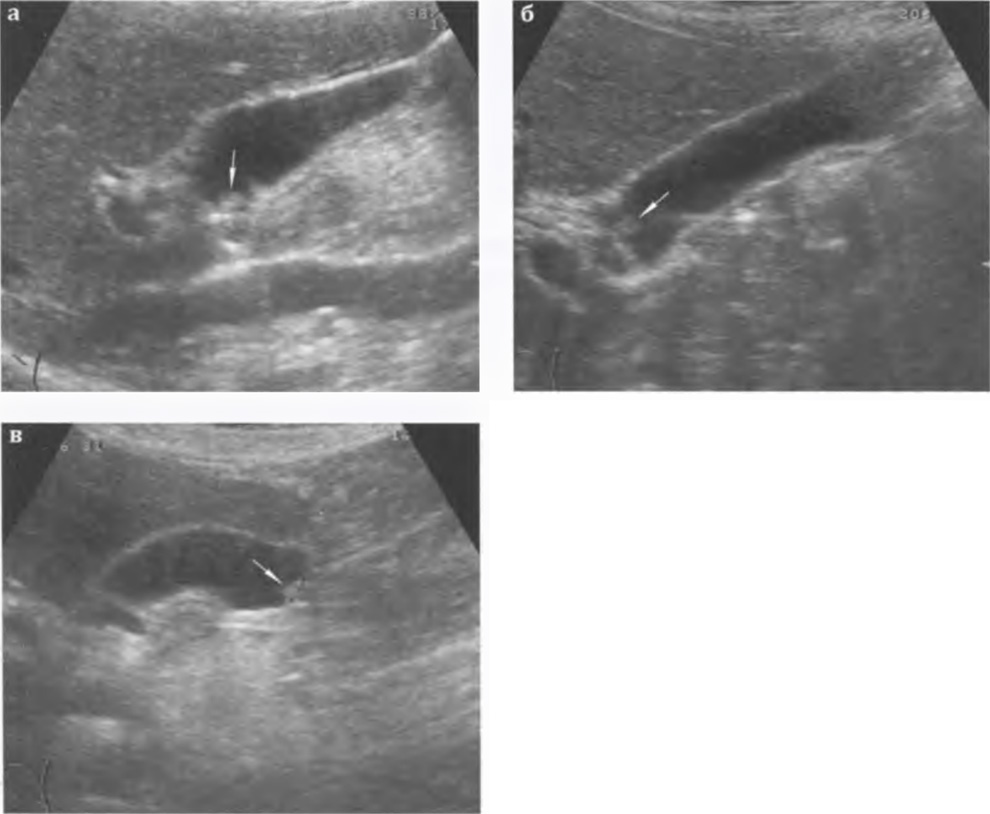

Хронический холецистит. Ультразвуковые признаки хронического воспаления желчного пузыря не столь очевидны, как признаки острого воспаления. Размеры пузыря могут не изменяться, увеличиваться (при нарушении оттока желчи), уменьшаться (при сморщивании и склерозе стенки). При гипертрофической форме хронического воспаления толщина стенки желчного пузыря в среднем составляет 0,3-0,4 см, а при атрофической форме не превышает 0,1-0,2 см. Эхогенность стенки повышается, часто неравномерно. Контур становится неровным за счет рубцовых изменений. В просвете могут определяться застойная желчь, взвесь, камни (рис. 3.11 а-г). Изменения в окружающих тканях и реакция лимфатической системы не выражены. Исходом хронического рецидивирующего холецистита может быть сморщивание пузыря и его склероз: размеры желчного пузыря уменьшены, стенка значительно утолщена, неравномерно повышенной эхогенности, полость приобретает щелевидную форму, в просвете может определяться сгущенная желчь и конкременты.

Рис. 3.11 а, б, в ,г. Хронический калькулезный холецистит: а,б,в - стенка желчного пузыря повышенной эхогенности, в просвете лоцируются конкременты; г - сморщенный желчный пузырь; стенка значительно утолщена (+...+), неравномерно повышенной эхогенности, просвет уменьшен, в просвете - сгущенная желчь и конкременты.